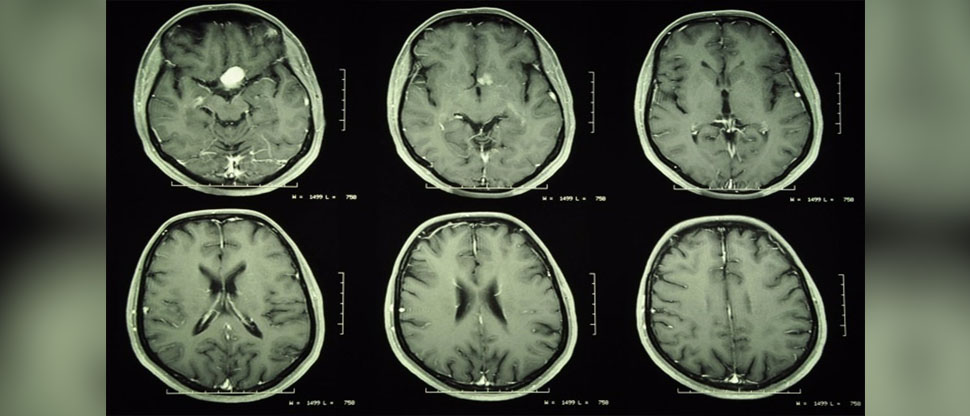

Un estudio publicado por el British Medical Journal reveló un grave riesgo para las mujeres que utilizan medicamentos con progesterona.

El artículo, retomado por Spectator, revela que el uso de este tipo de medicamentos en las mujeres incrementa el riesgo de padecer tumores cerebrales meningiomas.